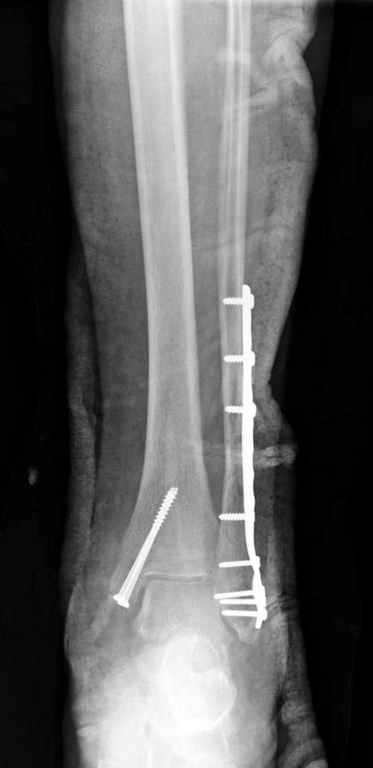

Удалены спицы, а гипса не было? 3-х лодыжечный перелом фиксировать 4 недели недостаточно. Что и подтверждается на последнем снимке - есть тенденция к подвывиху кнаружи, кзади... Что будет дальше, когда пациент начнет давать полную нагрузку?

СМ> На 4-й неделе убрал спицы, с 7-й недели начал ЛФК, дозированную

Малоберцовая выглядит коротковатой. Профиль как-то мутный. Вообще, неплохо было бы сделать снимки в сравнении со здоровой.

> Малоберцовая выглядит коротковатой. Профиль как-то мутный. Вообще,

> неплохо было бы сделать снимки в сравнении со здоровой.

> Малоберцовая выглядит коротковатой. Профиль как-то мутный.

Конечно, малоберцовая укорочена, надо сделать косой - мортиз снимок, тогда будеть понятно, на сколько.

Здесь финальный снимок 73 летней с

сопутствующей шизофренией, латерально бридж

пластину (соединили дистальный конец с диафизом не трогая место перелома) и медиально перкутанно

двумя шурупами. В этам случае без гипса не

обойтись.